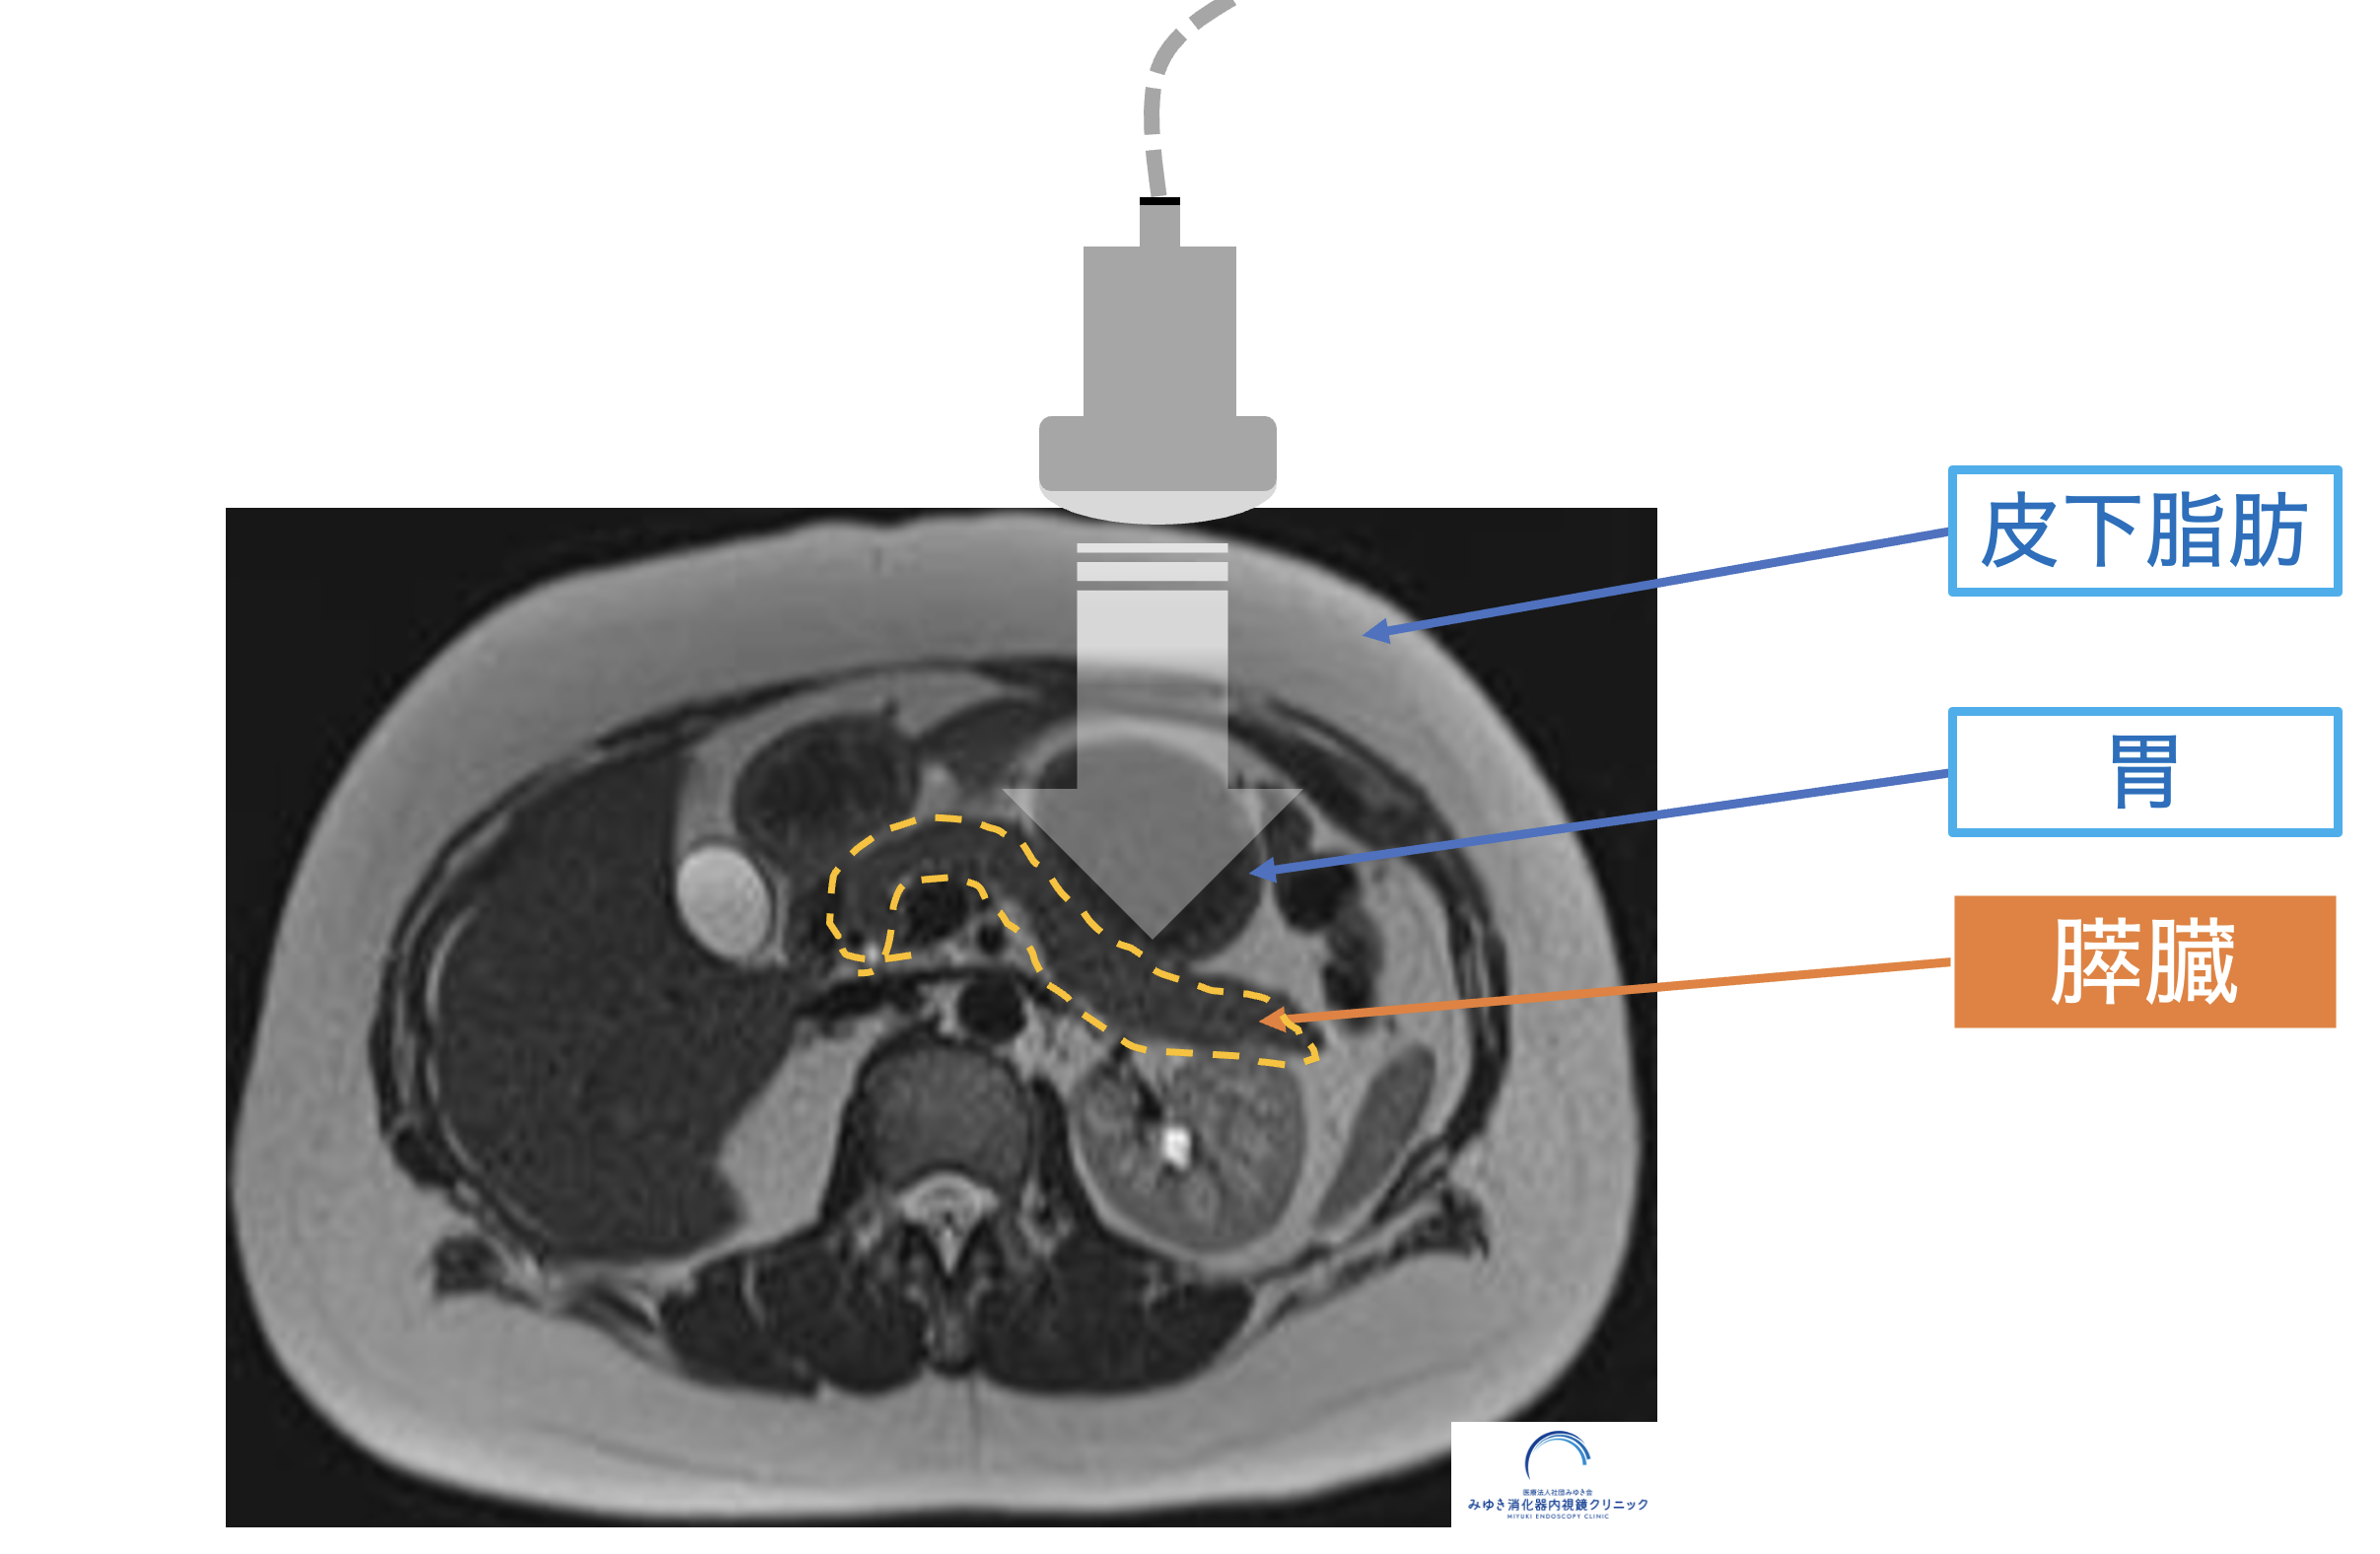

膵臓は胃の裏側(背中側)に位置しているため、皮下脂肪や内臓脂肪、胃や腸にたまったガスが超音波を遮り、十分に観察できないことがあります。

膵臓が胃や腸の奥に位置し腹部エコーで見えにくいことを示した図

膵臓は胃や腸の奥(背中側)に位置しているため、ガスや脂肪の影響で腹部エコーでは十分に観察できないことがあります。